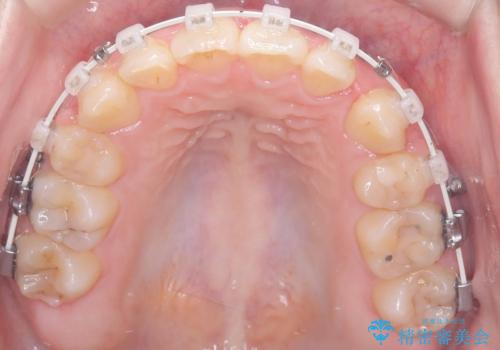

- 「歯のデコボコ、八重歯、口ボコが気になる」を主訴に来院された患者様です。

上下左右4番(4本)の歯を抜歯しワイヤー矯正で治療を行いました。

計4本の抜歯を行い、歯のデコボコと口元がすっきりし、大変ご満足していただけました。